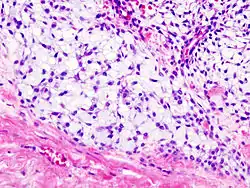

Imaging studies - including radiographs ("x-rays"), computerized tomography (CT), and magnetic resonance imaging (MRI) - are often used to make a presumptive diagnosis of chondrosarcoma.[11] However, a definitive diagnosis depends on the identification of malignant cancer cells producing cartilage in a biopsy specimen that has been examined by a pathologist. In a few cases, usually of highly anaplastic tumors, immunohistochemistry (IHC) is required.

Histopathology